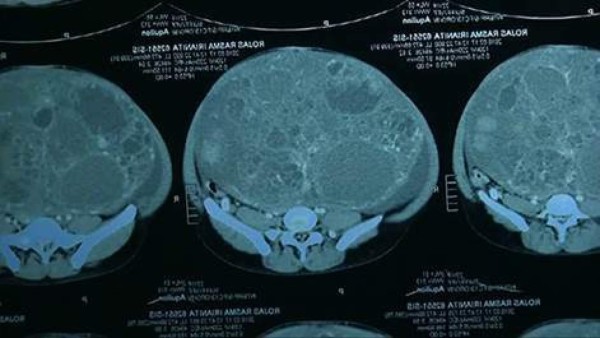

Un tumor de 16 kilos le fue extraído a una mujer de 22 años de edad por un equipo de médicos especialistas en Perú.

De acuerdo al informe medico, el tumor estuvo creciendo durante más de ocho años, y parecía que la joven, Iranita Rojas, estaba embarazada.

La dama vive en una comunidad rural en el noreste del país y fue transportada a Lima para la cirugía. Su caso fue descubierto durante una visita del ministro de Salud de ese país, Aníbal Velásquez, a la construcción de un nuevo hospital en la comunidad de Tamshiyacu, donde vive la mujer.